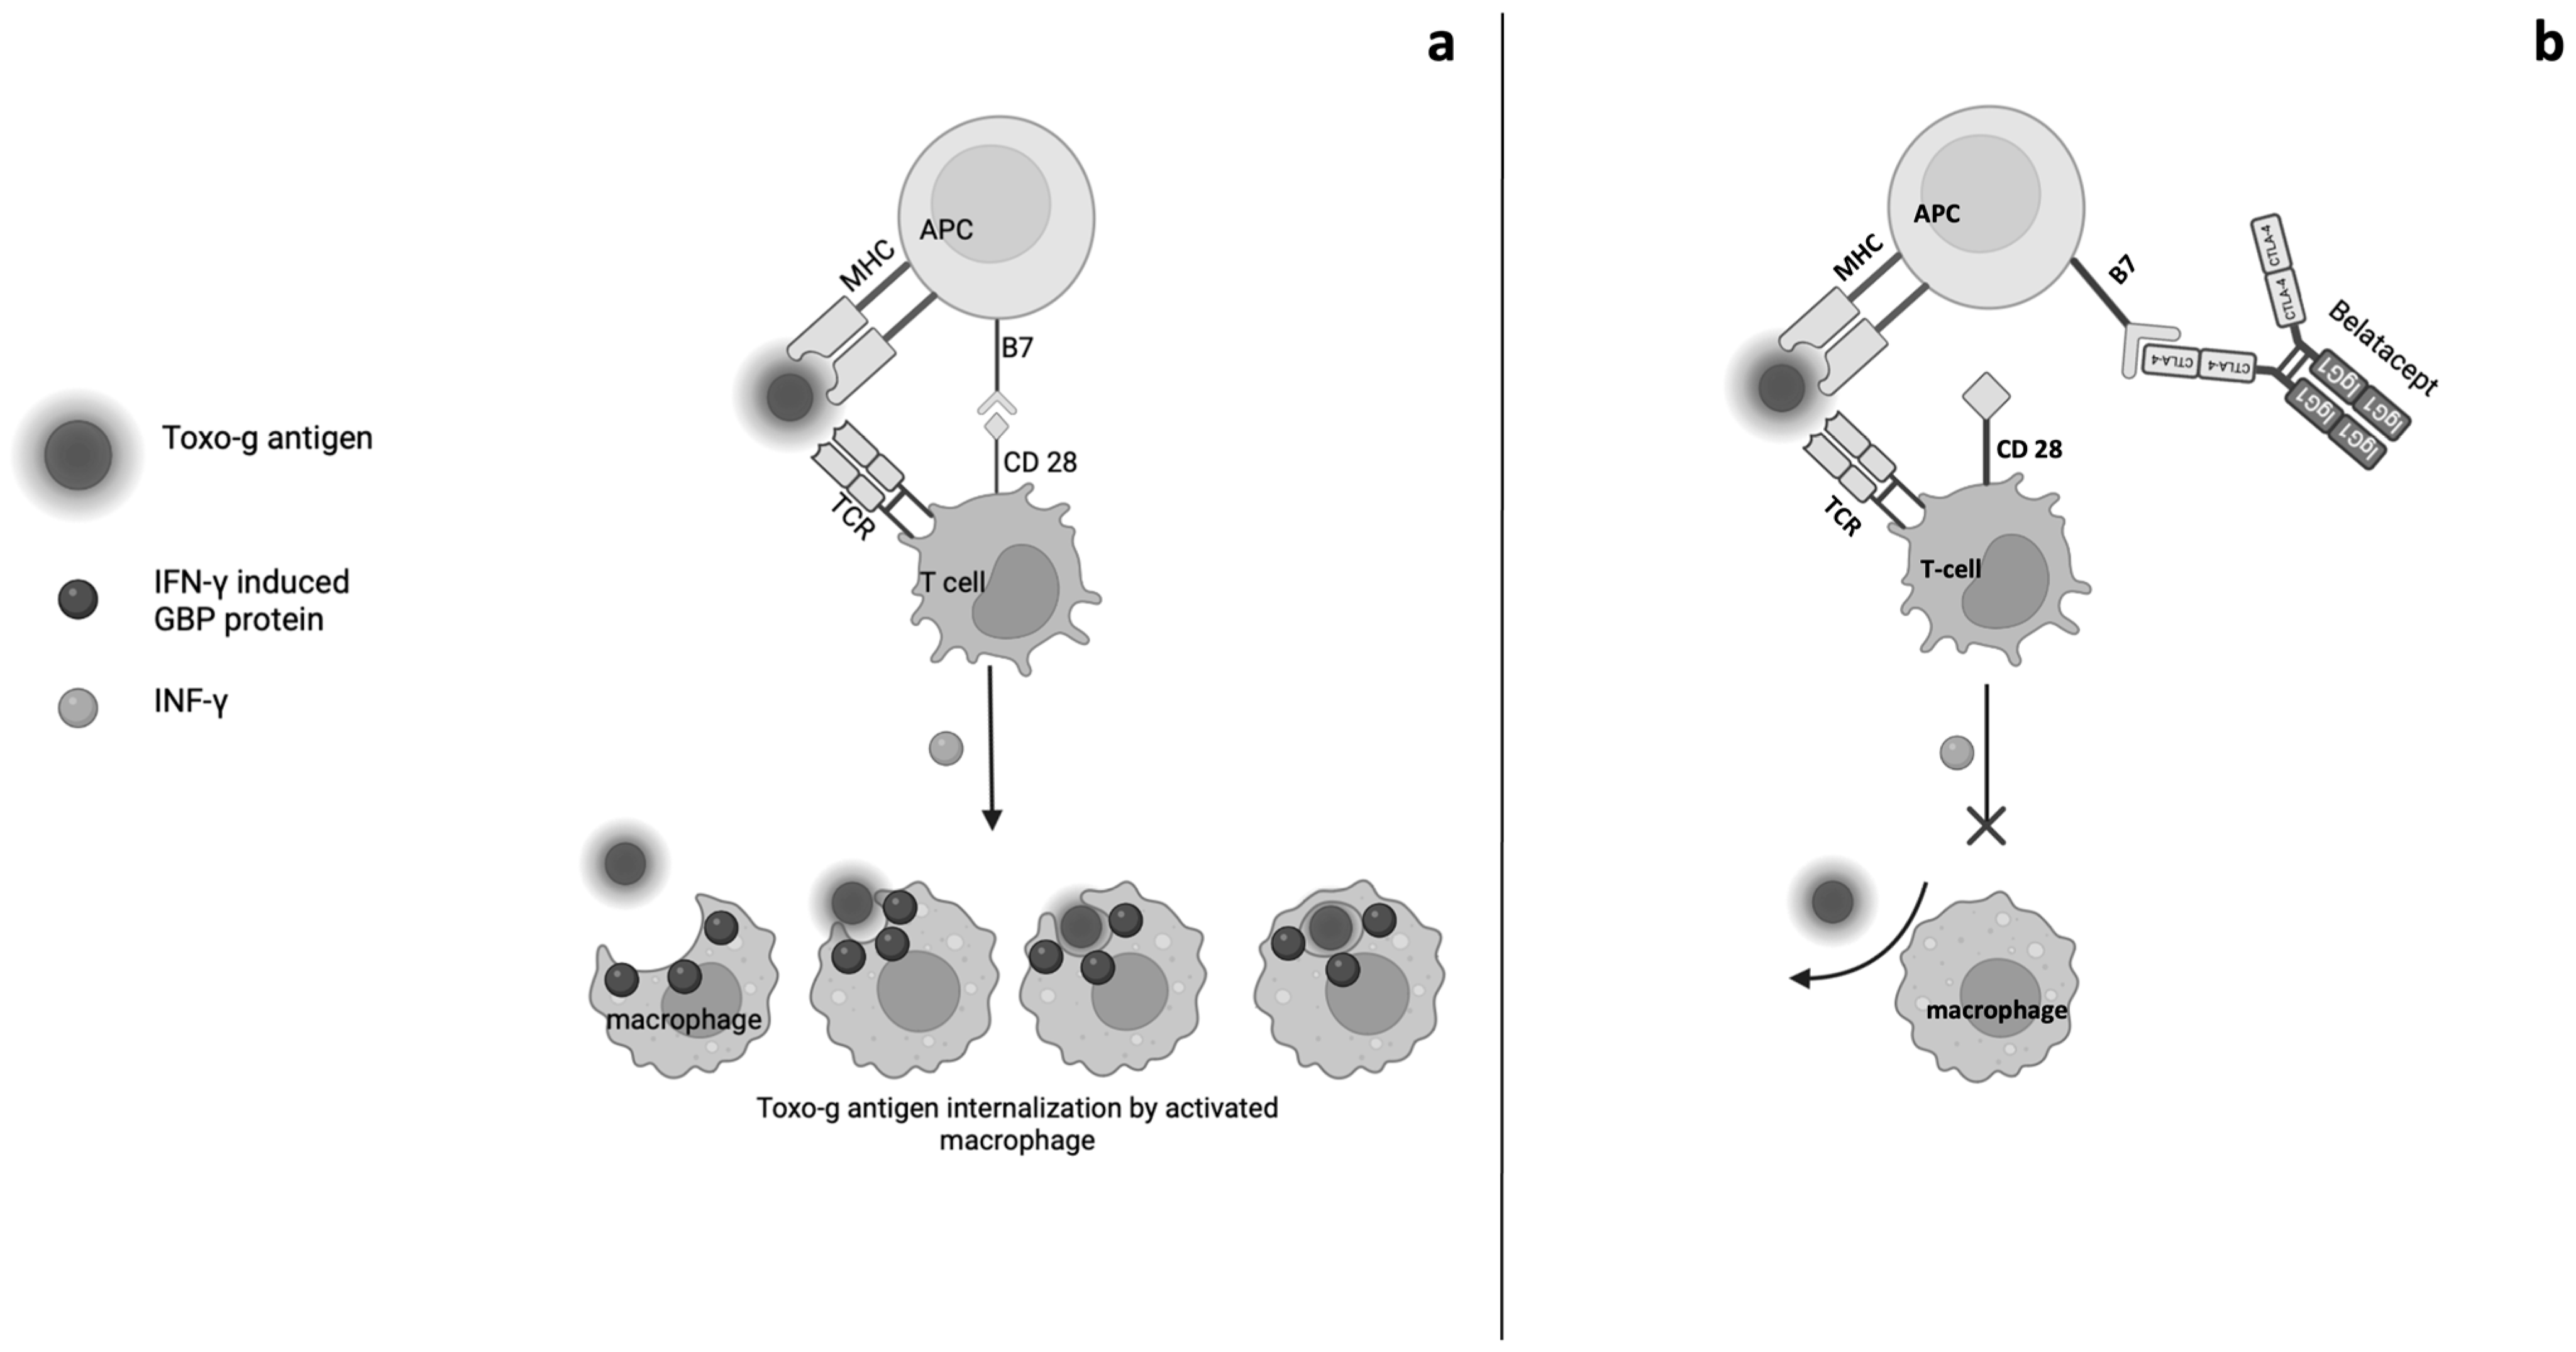

4. Adverse Events Related to Belatacept Treatment

5. Opportunistic Infections and Belatacept

- Schlüter, D.; Deckert, M.; Hof, H.; Frei, K. Toxoplasma gondii infection of neurons induces neuronal cytokine and chemokine production, but gamma interferon- and tumor necrosis factor-stimulated neurons fail to inhibit the invasion and growth of T Gondii. Infect. Immun. 2001, 69, 7889–7893. [Google Scholar] [CrossRef]

- Fisch, D.; Clough, B.; Khan, R.; Healy, L.; Frickel, E.M. Toxoplasma-proximal and distal control by GBPs in human macrophages. Pathog. Dis. 2022, 79, ftab058. [Google Scholar] [CrossRef]

- Santos, J.; Brož, P. Sensing of Invading Pathogens by GBPs: At the Crossroads between Cell-Autonomous and Innate Immunity. J. Leukoc. Biol. 2018, 104, 729–735. [Google Scholar] [CrossRef]

- Tretina, K.; Park, E.; Mamińska, A.; MacMicking, J. Interferon-Induced Guanylate-Binding Proteins: Guardians of Host Defense in Health and Disease. J. Exp. Med. 2019, 216, 482–500. [Google Scholar] [CrossRef]

- Kutsch, M.; Coers, J. Human Guanylate Binding Proteins: Nanomachines Orchestrating Host Defense. FEBS J. 2021, 288, 5826–5849. [Google Scholar] [CrossRef]